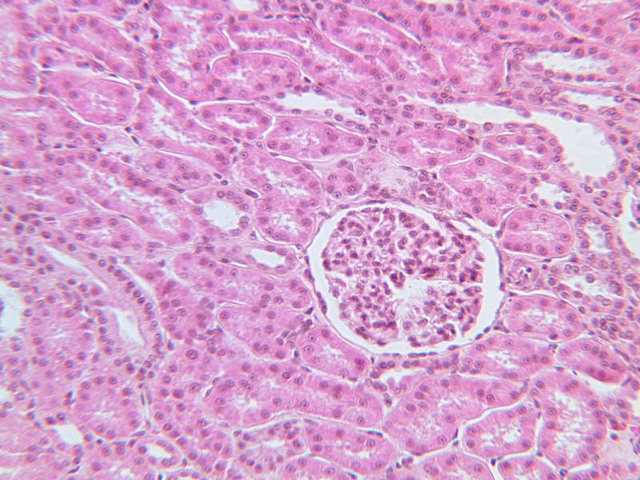

DistalConvolutedTubule (DCT): Description

DistalConvolutedTubule (DCT): Sections

B67, DCT, 10x (H&E) B67, DCT, 20x (H&E) B67, DCT, 40x Labeled (H&E) B68, DCT, 10x (PAS) B68, DCT, 20x (PAS) B68, DCT, 40x Labeled (PAS) B69, DCT, 10x (PAS) B69, DCT, 20x (PAS) B69, DCT, 40x Labeled (PAS) B71, DCT, 10x (H&E) B71, DCT, 20x (H&E) B71, DCT, 40x Labeled (H&E)

DistalConvolutedTubule (DCT): Identifications